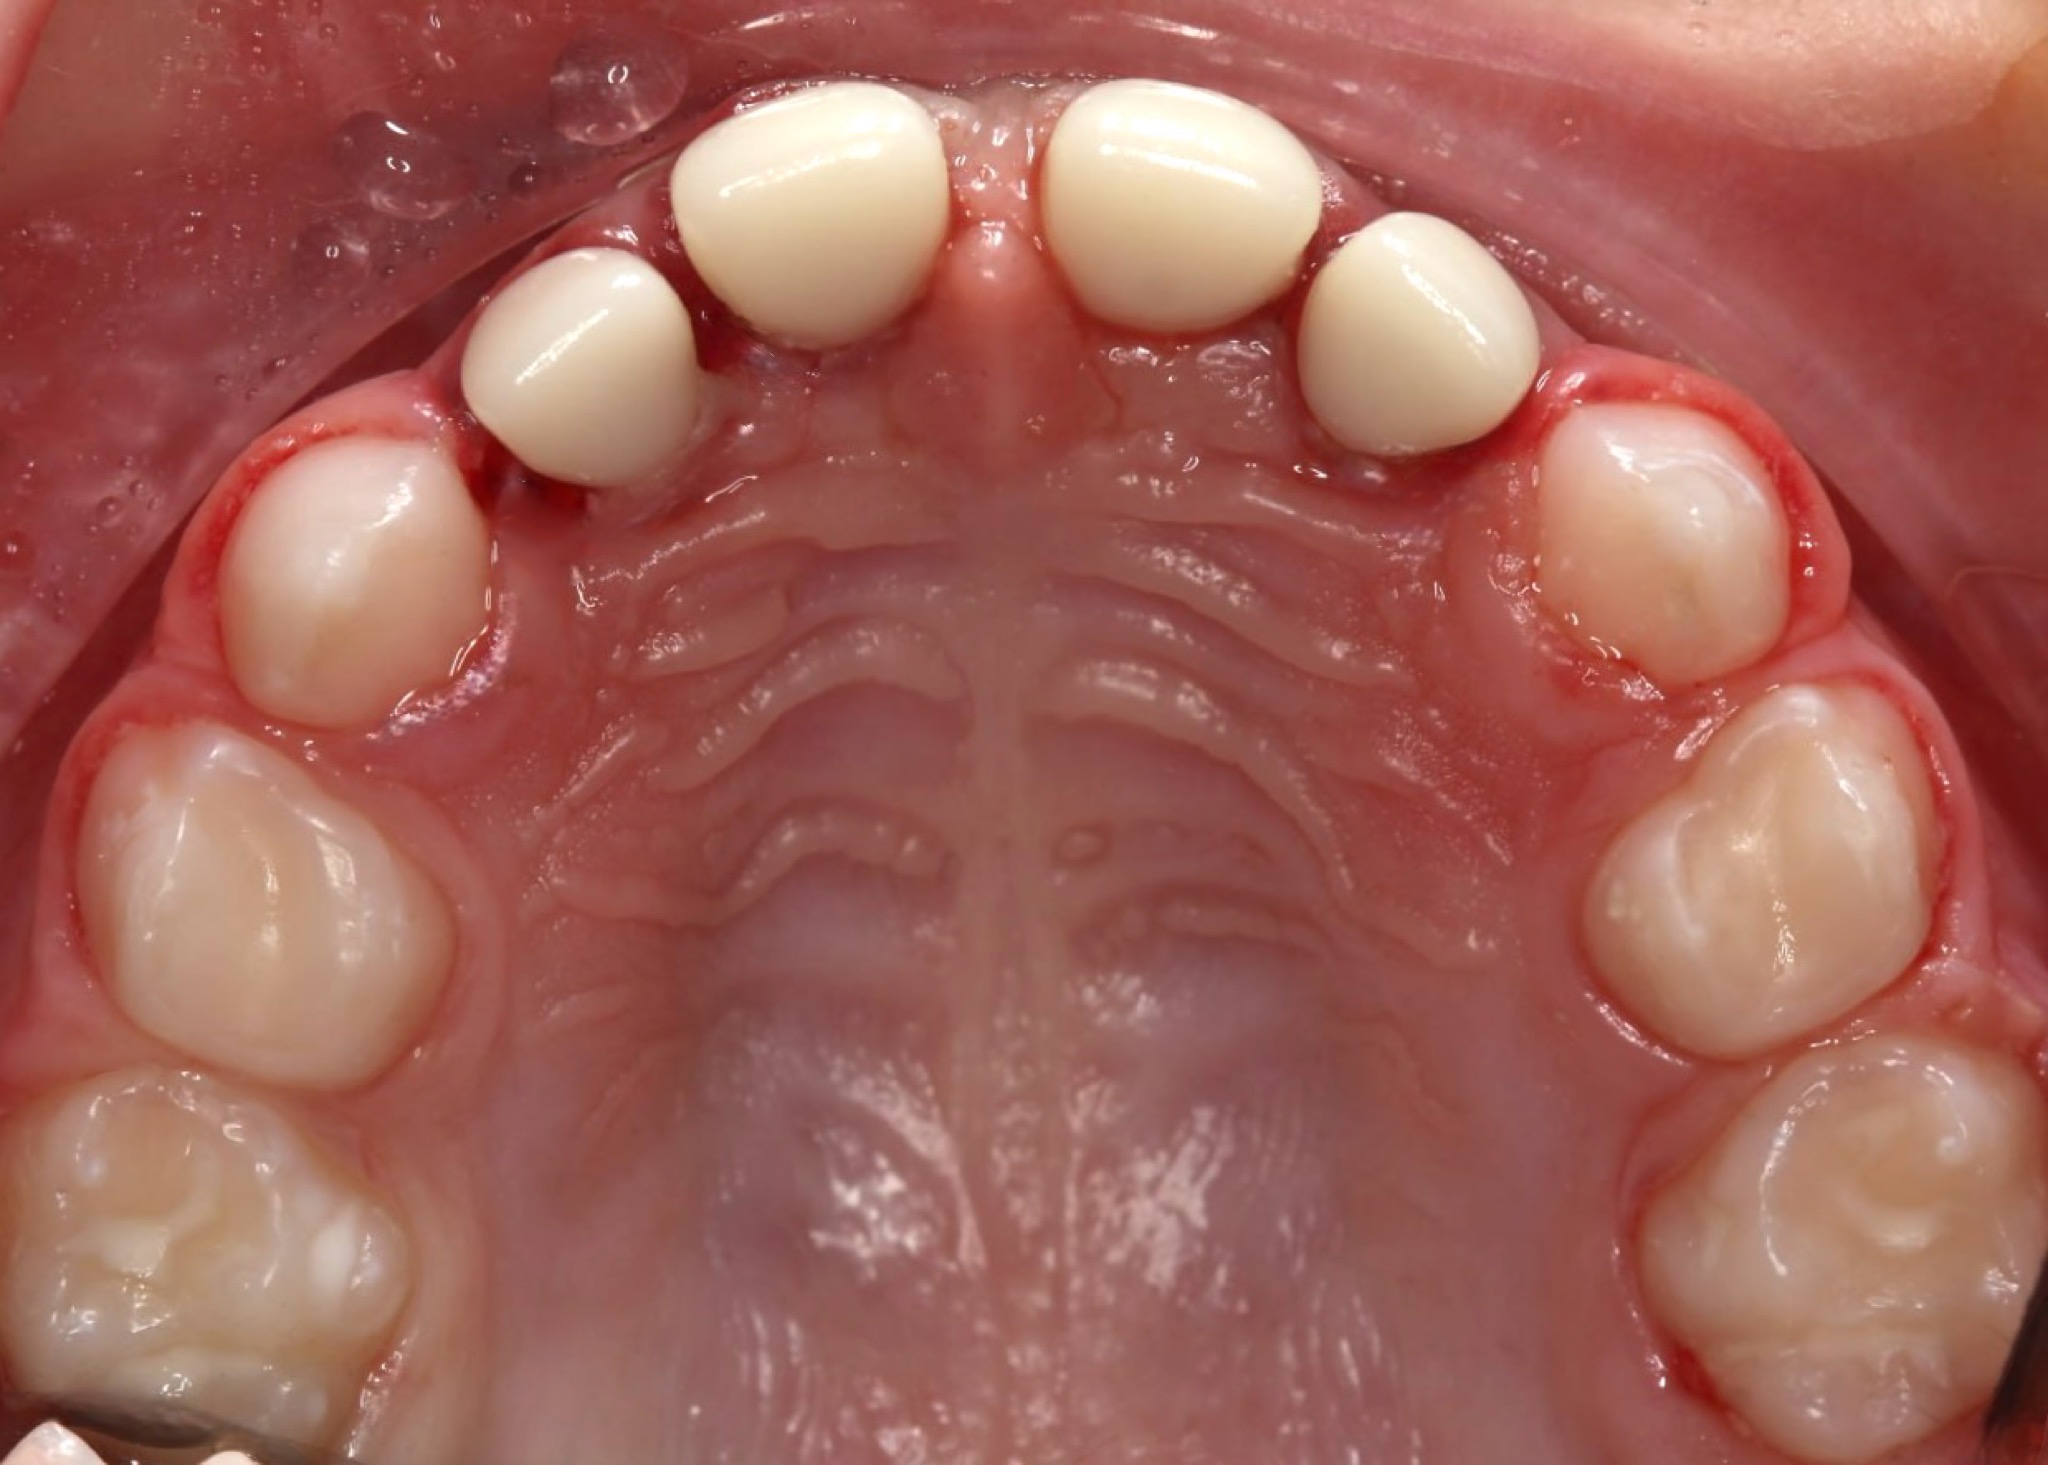

Ортодонтичне лікування: перший етап

Дитина звернулася до нашої клініки разом із батьками зі скаргами на неправильний прикус. Під час первинного огляду було встановлено, що для досягнення правильного змикання зубів необхідно розпочати лікування з підготовчого етапу.

На представленому фото — результат після першого етапу лікування, на якому вже помітні позитивні зміни прикусу.

Як проходив перший етап лікування

На першому етапі було виконано розширення верхньої щелепи. Для цього дитині встановили незнімний розширювальний апарат на верхню щелепу, який дозволяє:

• створити достатній простір для правильного розташування зубів;

• покращити співвідношення щелеп;

• підготувати зубощелепну систему до наступних етапів ортодонтичного лікування.

Вже після завершення цього етапу прикус почав змінюватися, що є важливим показником ефективності лікування.

Поточний стан і подальший план

На даний момент дитина носить лицьову маску, яка допомагає скоригувати ріст щелеп і закріпити отриманий результат. Після завершення цього етапу планується подальше лікування з використанням брекет-системи для точного вирівнювання зубів і стабілізації прикусу.

Ортодонтичне лікування у дітей часто проходить поетапно, і саме ранній початок дозволяє досягти більш прогнозованого та стабільного результату в майбутньому.